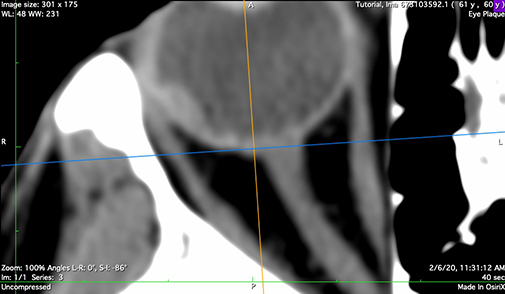

CT (or MR) Imaging

An orbital CT series, using a CT technique optimized for contrast of soft tissues (ie DO NOT use a bone imaging technique) with slice thickness <= 1 mm is the best option to model the eye for posterior and equatorially located tumors. MRI provides an acceptable alternative for ciliary and iris tumors when thin slices are available.

The orbital CT (or MRI) series is used to create these seven reconstructions that are used to build the 3D model of the eye. That 3D model is used to calibrate the fundus image, measure the optic nerve sheath diameter, and determine suture eyelet coordinates on the eye. If the tumor happens to be large enough to be visible in these reconstructions, the CT also provides confirmation of tumor location, shape and elevation as determined from the fundus and ultrasound imaging.

t-meridian

Meridian reconstruction through the tumor apex.

n-axial

Axial bisector illustrating the nerve-coronal plane (blue axis)